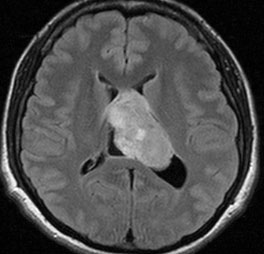

70歳女性に偶然発見された例

- 偶然発見されたものには増大しないものがあります

- 無治療で経過観察してよいものがあります

incidental tumor 偶発腫といいます。病理診断はないのですが,まず間違いなくcentral neurocytomaで,数年間の観察で全く増大しませんでした。高齢の患者さんでは無症候で発見し,経過を見ていくと嚢胞変性を来たし,自然退縮していくものも見られす。この例でも,左のモンロー孔は閉塞していて,左側脳室は水頭症となっていますが,無症候です。おそらくこの腫瘍は今後も症候性となることはありません。センロラルニューロサイトーマは,神経鞘腫と同様に加齢によって変性し退縮する自然歴を有している腫瘍です。